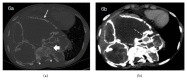

Giant cell tumor of bone (GCT) is a rare, locally aggressive neoplasm characterized by the presence of giant cells with osteoclast activity. Its biology involves the overexpression of the Receptor Activator of Nuclear Factor kB Ligand (RANKL) by osteoclast-like giant cells and tumor stromal cells, which has been shown to be an actionable target in this disease. In cases amenable to surgical resection, very few therapeutic options were available until the recent demonstration of significant activity of the anti-RANK-ligand monoclonal antibody denosumab. Here we present a case of a patient with advanced GCT arising in the spine, recurring after multiple resections and embolization. Following initiation of denosumab, which resulted in unequivocal clinical improvement, computed tomography of the chest done for reassessment purposes revealed an intratumoral pseudoaneurysm by erosion of the aorta, further corrected by endovascular approach and stent placement. Patient had an unremarkable recovery from the procedure and continued benefit from therapy with denosumab and remains on treatment 24 months after the first dose.